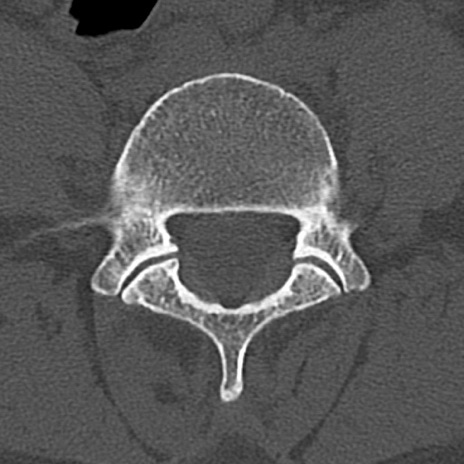

腰椎CT

横断像と矢状断像